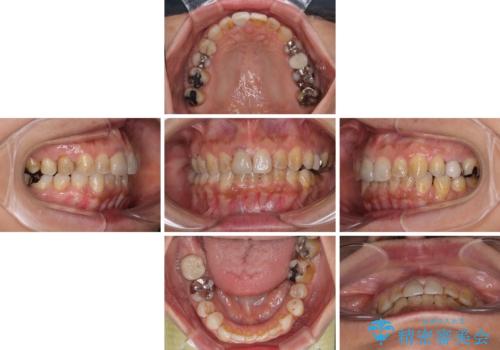

- 上下前歯のデコボコと、治療途中の歯を気にして来院された患者様です。

ご家族がインビザラインにて矯正治療を行っていたため、ご本人の希望によりインビザラインによるマウスピース矯正を行うこととしました。

根管治療が必要な歯は事前に処置を行った上で矯正治療を開始し、概ね歯列が整ったところでセラミッククラウンなどに置き換え、その後インビザラインを1セット使用して仕上げていくこととしました。

痛みがなくなり歯列が整ったことで、残っている銀歯も気になり始めているようです。

マウスピース生活に疲れてしまったとのことで、暫くお休みをしてから銀歯の治療を再開していく予定です。